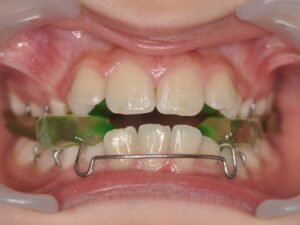

L'AXE DES FONCTIONS BUCCALES

Il s’agit de la mastication, la respiration, la posture linguale, les habitudes déformantes. Elles font partie intégrante de la bonne posture des mâchoires et des dents. Elles seront également contrôlées et interceptées. Les appareils sont nombreux en fonction de la malocclusion, ils peuvent être fixes ou amovibles. Très souvent, l’interception pourra être associée à un rendez-vous chez : l'ORL, l'orthophoniste, le kinésithérapeute ou encore l'osthéopathe.

En phase active de traitement, certains seront à porter 24 heures sur 24 et d’autres en rentrant de l’école et toute la nuit.

L’orthodontiste vous donnera des conseils en fonction de l’appareil que l’on vous aura remis et donc de votre situation clinique.